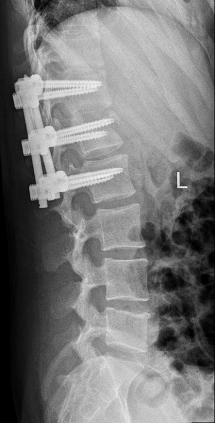

术后影像显示,螺钉位置良好